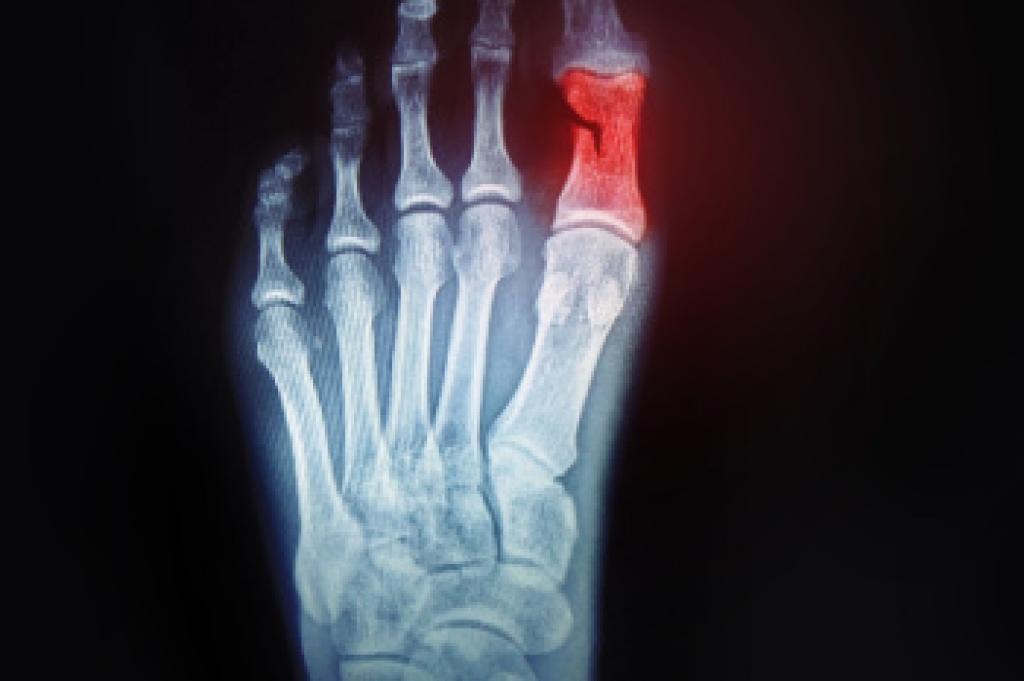

A broken toe is a fracture of one of the small bones in the toe, often caused by direct trauma or excessive force. This injury may occur from stubbing the toe, dropping a heavy object on the foot, or experiencing a sports-related accident. Common symptoms include sharp pain, swelling, bruising, tenderness, and difficulty walking. In some cases, the toe may appear misaligned or feel stiff. Diagnosis is typically made through a physical examination and confirmed with an X-ray to determine the extent of the fracture. A podiatrist can provide proper treatment, stabilization, and guidance for healing. If you have sustained a toe injury, it is suggested that you consult a podiatrist who can provide an accurate diagnosis and effective treatment solutions.

A broken toe occurs when one or more of the toe bones of the foot are broken after an injury. Injuries such as stubbing your toe or dropping a heavy object on it may cause a toe fracture.